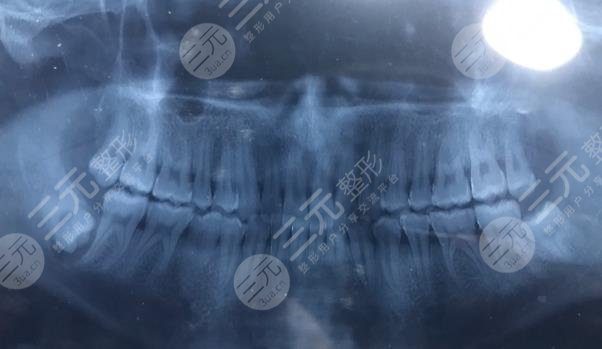

智齿已经长了好多年了,痛起来真的是整个半边脸都是肿的,饭不能吃,喝口水都疼,不是没去过医院,医生照了片跟我说,智齿长的位置不好,在牙龈里面很深的地方,动不了手术,回去吃消炎药止疼药吧,我?后来有朋友建议不如去深圳美奥口腔医院看看,那里的医术还挺好的,抱着试一试的态度去的,没想到医生说的完全不一样,告诉我可以手术处理,只是难度比较大,然后就为我预约了手术,整个手术过程医生说很顺利,其实我知道,我是遇到好医生了,为我解决了困扰多年的问题。到现在已经缓解半年了,完全不痛了。